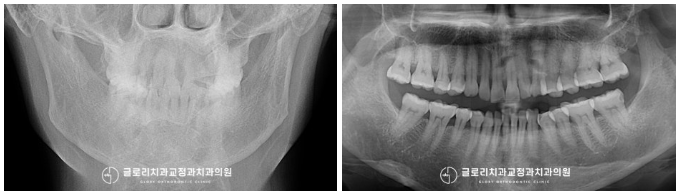

방사선 촬영으로 정밀검진을 시행하여

치근흡수나 치주 질환 등

다른 문제들이 없는지 꼼꼼하게 확인하는데요.

다행히 치열 개선을 진행해도

문제가 없을 거라는 판단이 들어

본격적으로 계획을 세우기로 했습니다.